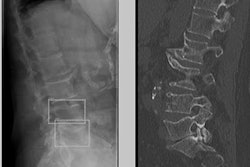

In the study, Guermazi and colleagues evaluated a model developed by Gleamer.ai based on a dataset of 60,170 radiographs of patients with trauma from 22 institutions. They found that the algorithm improved fracture detection by radiologists and six other types of readers by 10.4% and cut reading time by 6.3 seconds per patient.